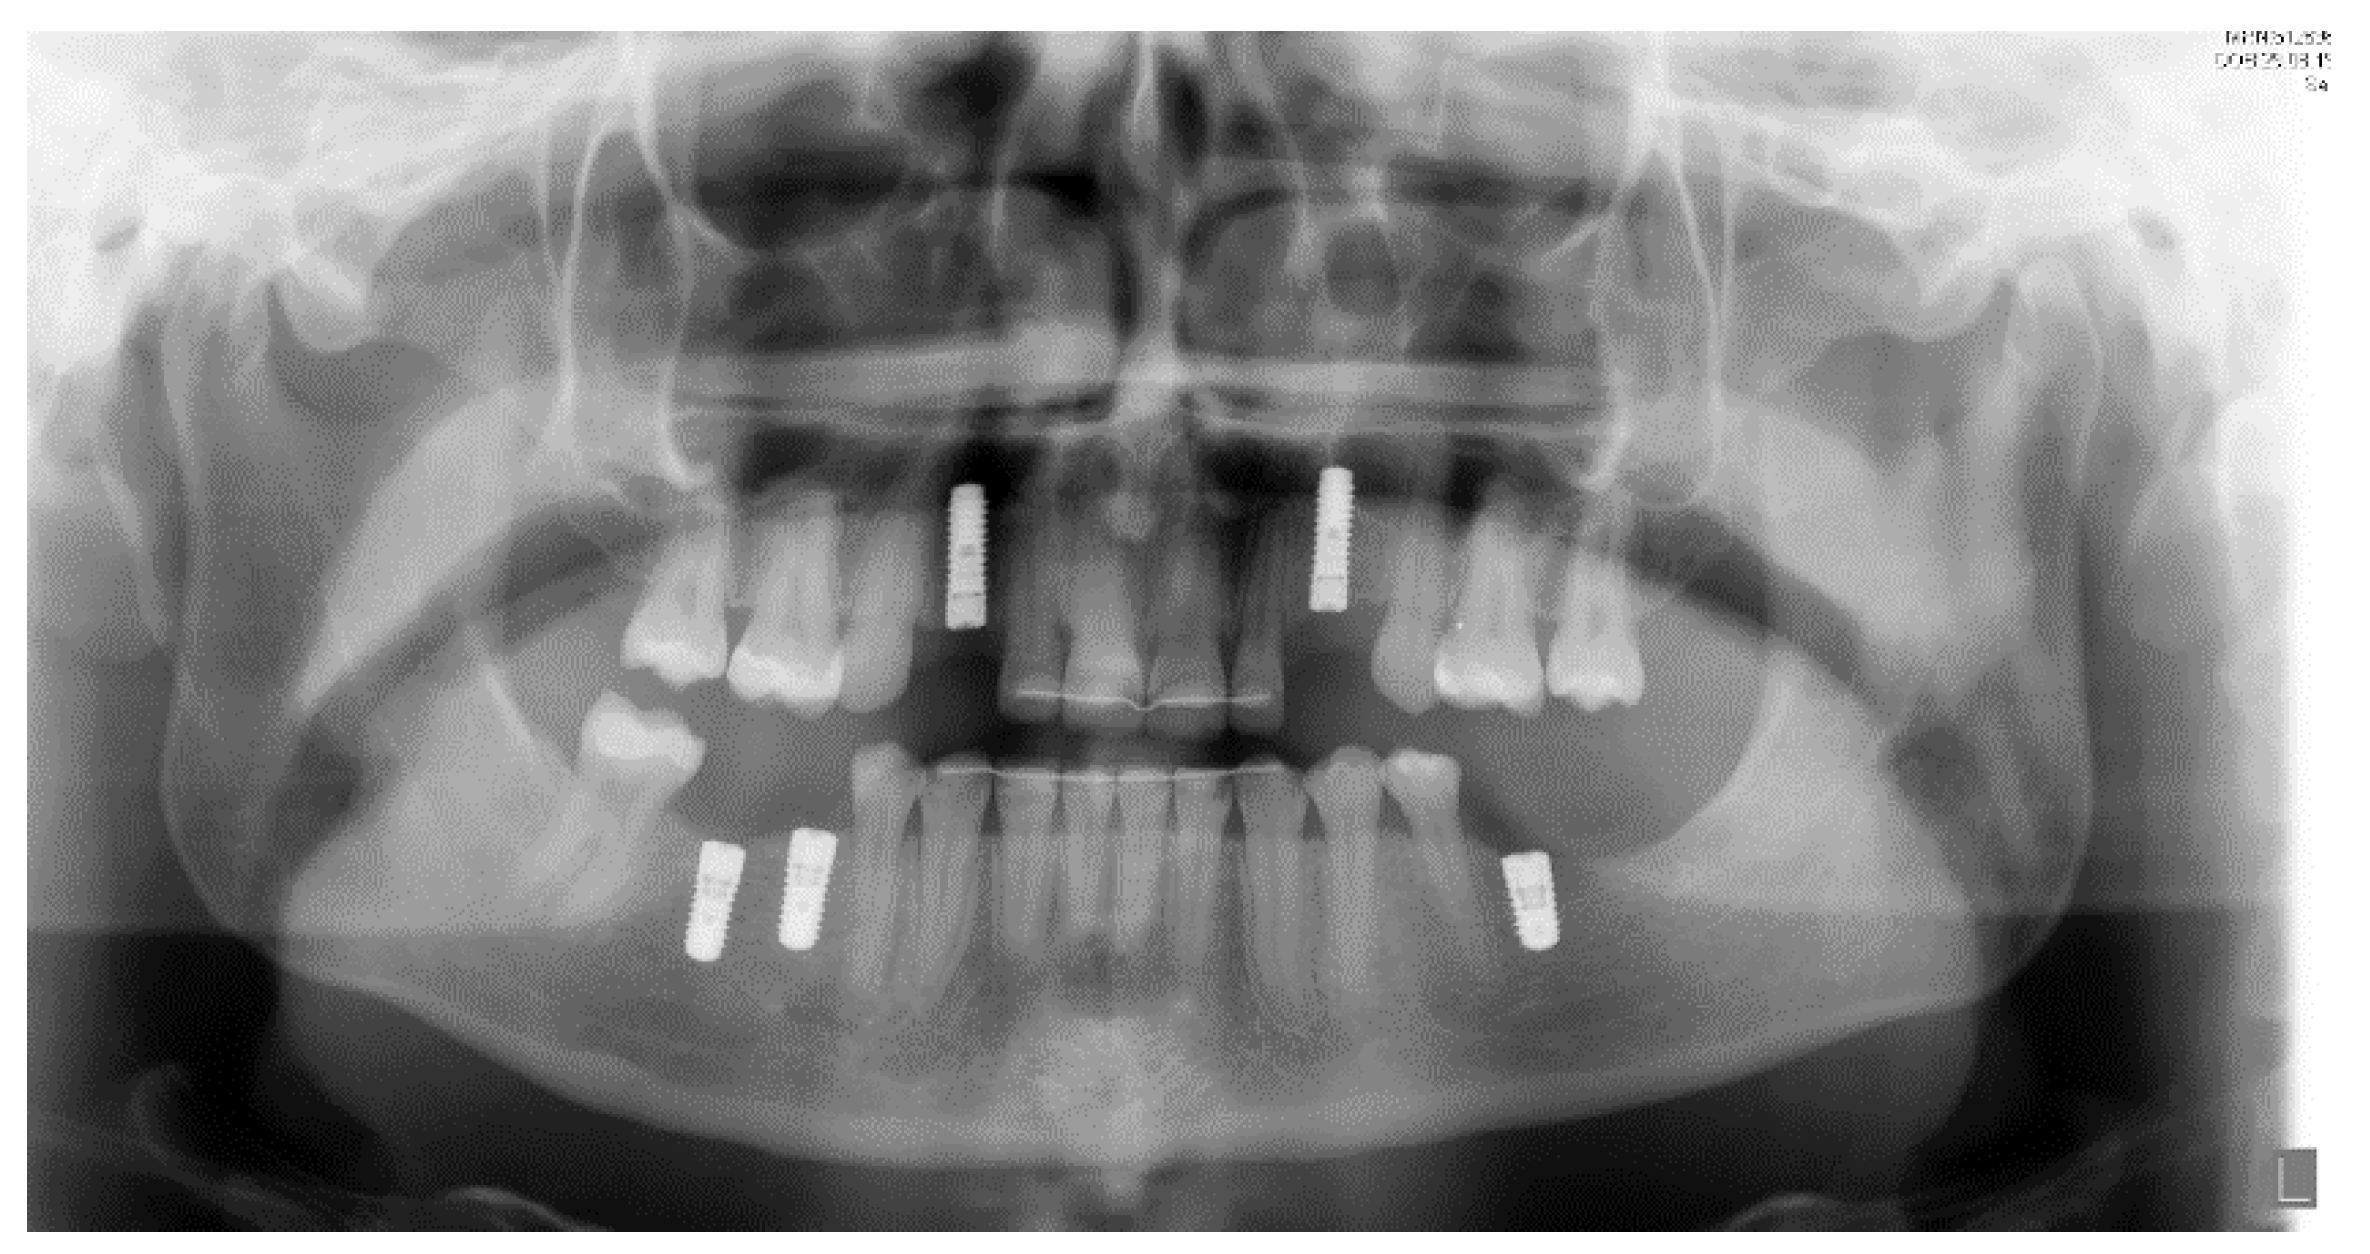

Figure 7.

Initial panoramic radiography.

Titanium dental implants (Bone Level, 3.33 × 12 mm and 4.1 × 8–10 mm, Straumann, Basel, Switzerland) were placed under local anesthesia (Septanest 1:200,000) at sites 13, 23, 36, 45, 46, using the surgical guide as reference. After a healing period of three months, implant-supported porcelain crowns were installed with a torque strength of 35 Ncm. Additionally, teeth 13 and 23 were prepared for a crown with shape of premolar teeth, and porcelain crowns were cemented using resin cement (RelyX, 3M, Neuss, Germany). The treatment showed satisfactory aesthetic and functional results at 1-year follow-up. Dental implants were osseo-integrated without marginal bone loss (Figure 10 and Figure 11).